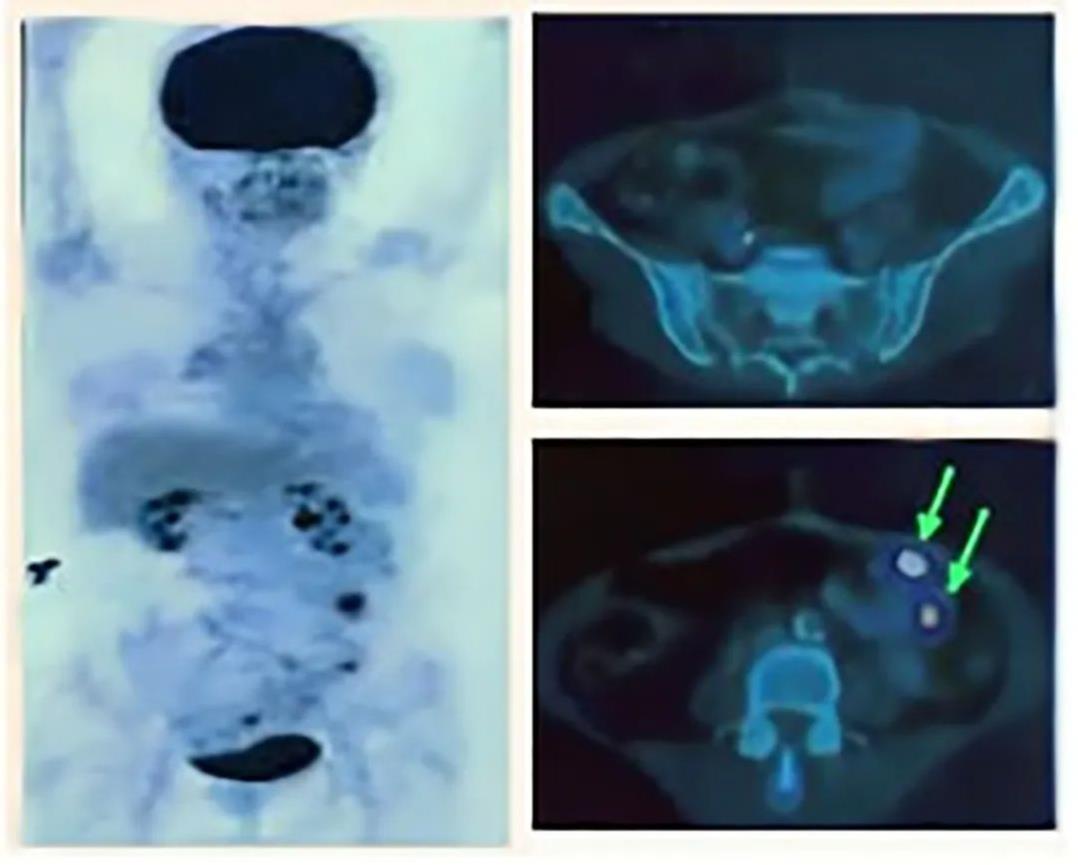

2、横结肠切除术后3年,NK细胞治疗后:PET扫描显示,在轴向视图上,局部转移灶中不再有氟脱氧葡萄糖摄取,且腹腔内未见额外的摄取(详见下图)。这也意味着患者病情好转,且局部区域未见复发的征象(截至2022年12月下旬)。此外,该患者无长期心肺发病率,可进行正常的日常活动。

▲图源“Cancer Rep”,版权归原作者所有,如无意中侵犯了知识产权,请联系我们删除